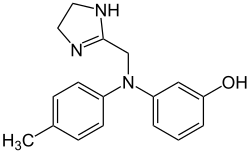

| Phentolamine | Regitine |

Competitive blocking of α1 and α2 receptors. | Reversal of epinephrine induced effects.

Lowers blood pressure by decreasing peripheral resistance.[2][10] |

Phentolamine, a non-selective alpha blocker, has also been tested to treat erectile dysfunction. By reducing vasoconstriction in the penis, there appears to be increased blood flow that aids in penile erection. Side effects associated with phentolamine include headache, flushing, and nasal congestion.[23]

There are some alpha blockers that can give rise to changes in the cardiovascular system, such as the induction of reflex tachycardia, orthostatic hypotension, or heart palpitations via alterations of the QT interval.[28][31] Alpha blockers that may have these side effects include yohimbine, phenoxybenzamine, and phentolamine.[2]

As with any drug, there are drug interactions that can occur with alpha blockers. For instance, alpha blockers that are used for the reduction of blood pressure, such as phenoxybenzamine or phentolamine can have synergy with other drugs that affect smooth muscle, blood vessels, or drugs used for erectile dysfunction (i.e. sildenafil, tamsulosin, etc.). This stimulates exaggerated hypotension.[2]